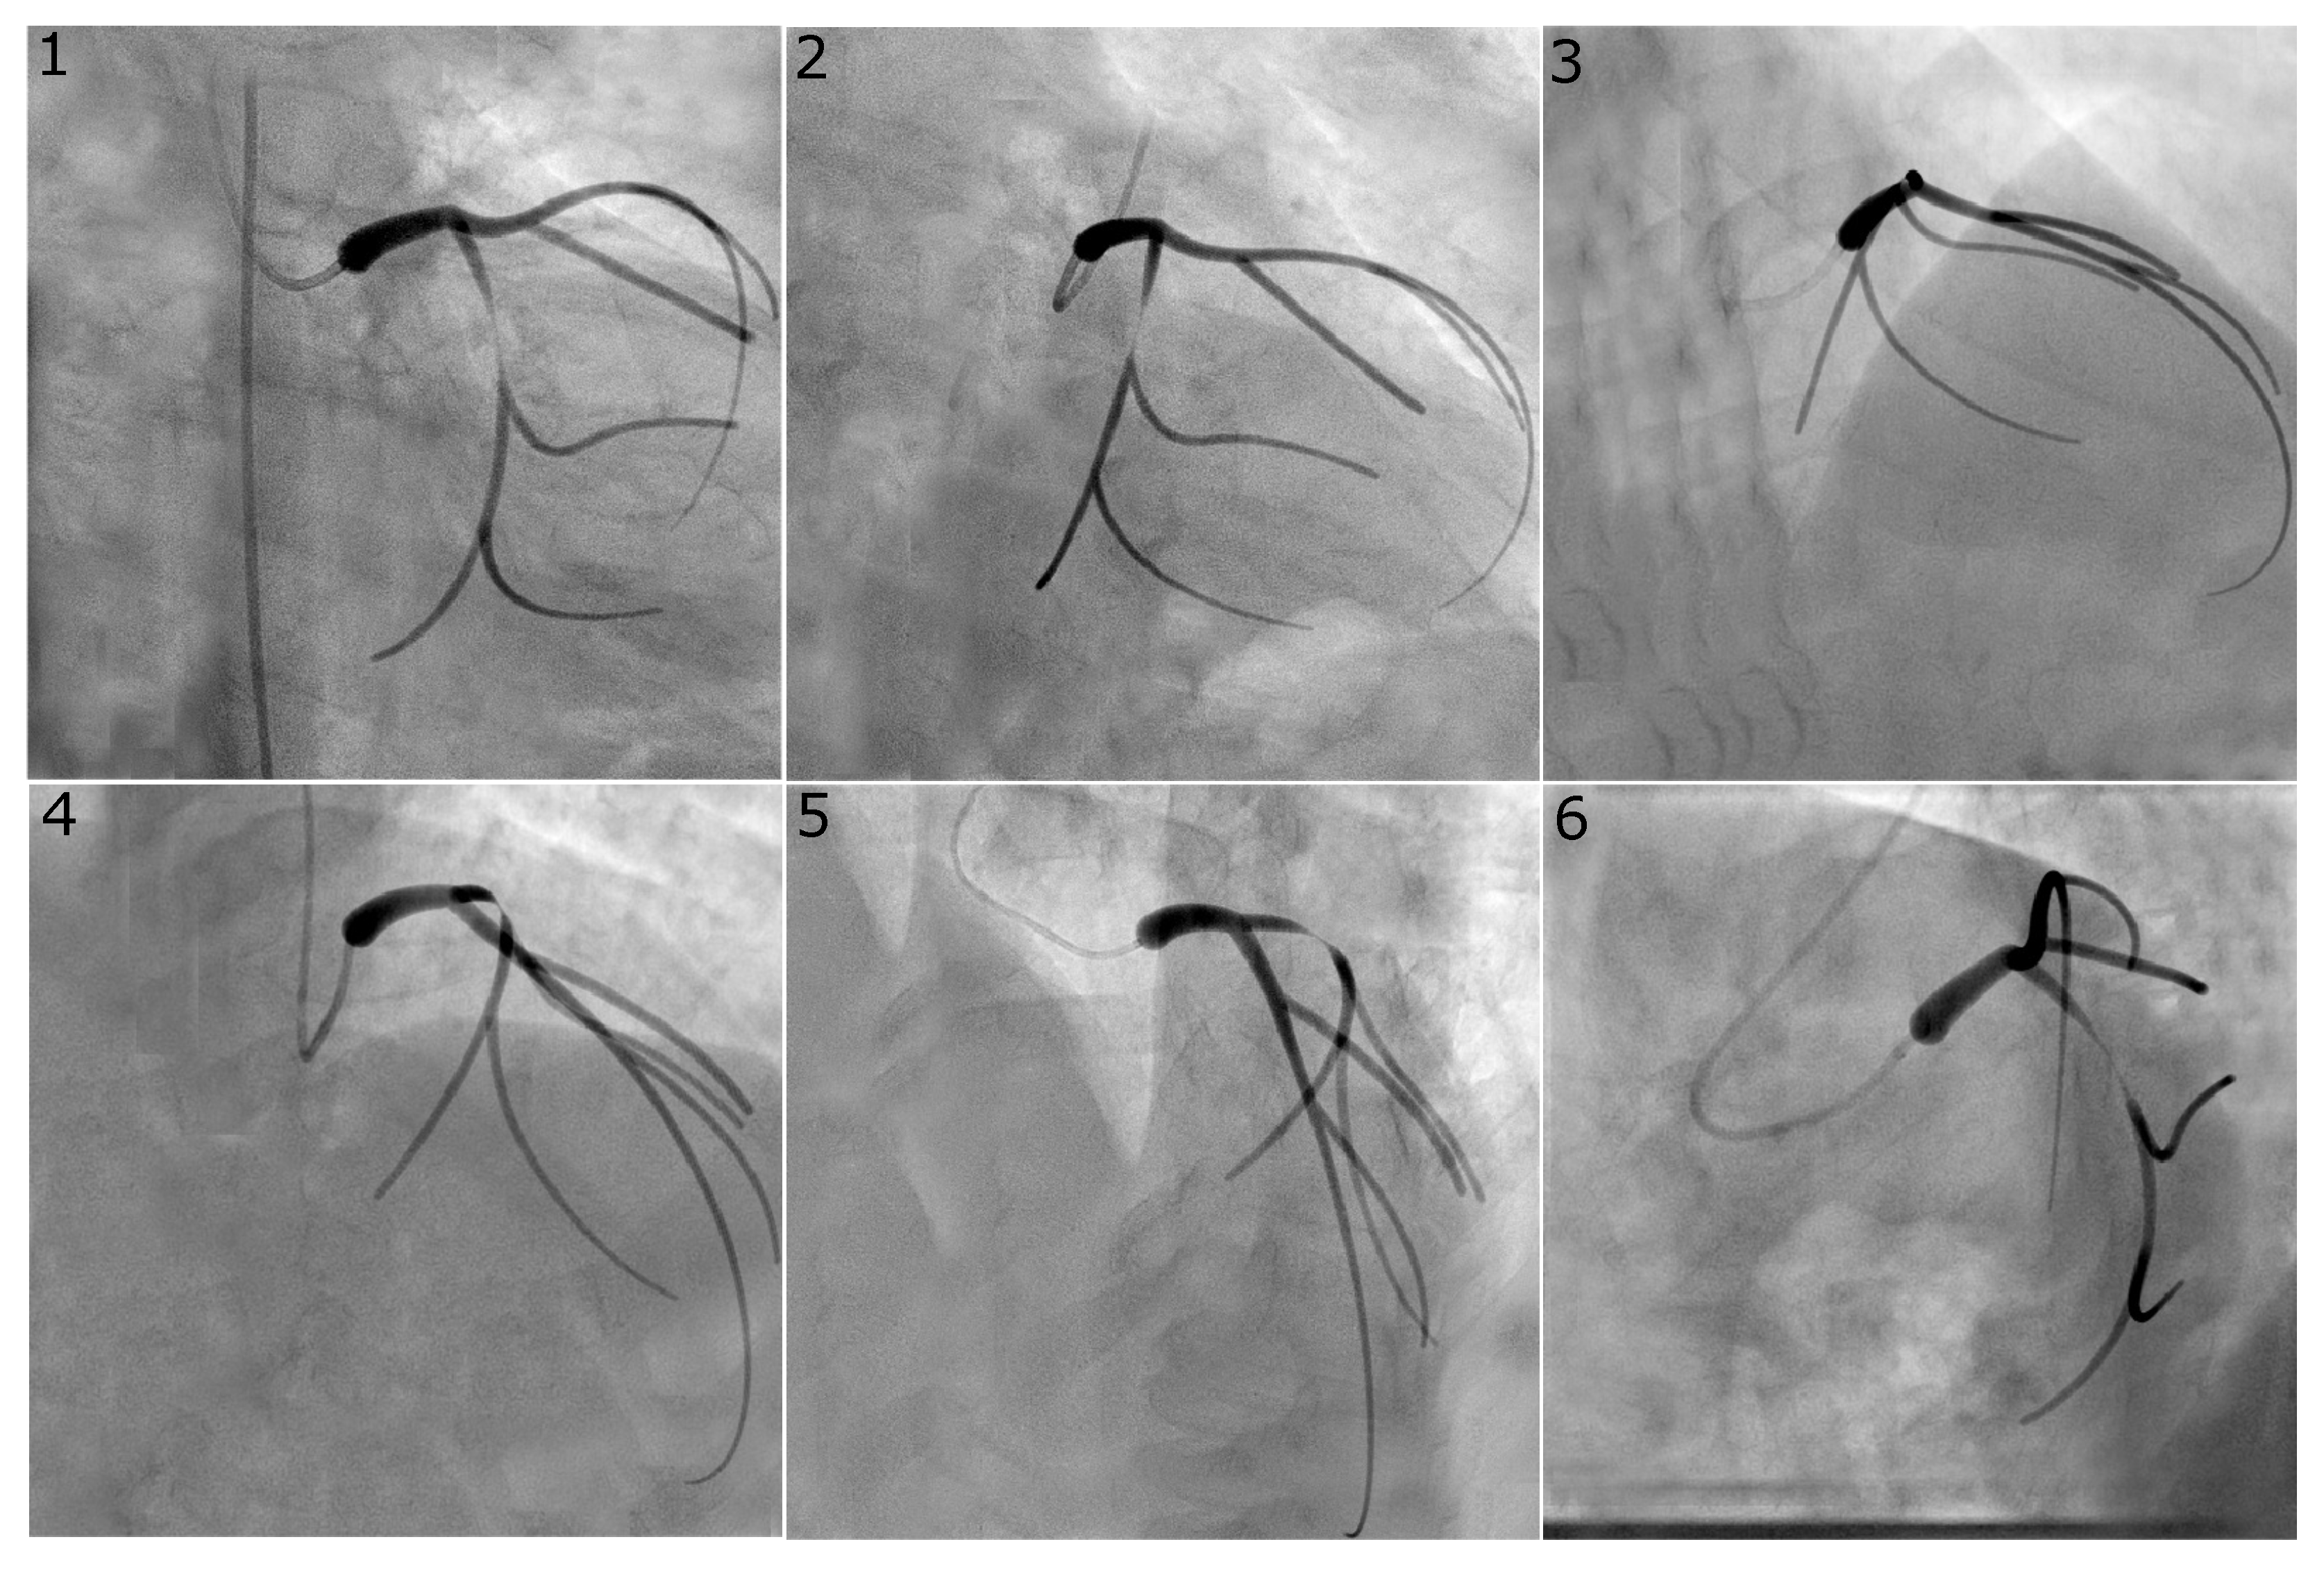

Figure 2.

Virtual angiogram for all views of the left coronary system with a concentric stenosis of diameter reduction in the LCX. Views , and were used to reconstruct this vessel as they are usually selected in the catheterisation laboratory since they avoid vessel overlap and excessive foreshortening for the vessel of interest.

Figure 2 and Figure 3 show representative examples of virtual angiograms generated for the two coronary arteries considered in this study. Figure 2 shows the case in which a concentric stenosis, of diameter reduction, affects the LCX. This case is included here for theoretical interest as it allows for an appreciation of the severity of a stenosis of this diameter reduction, but it is of smaller concern to the clinical community, due to the certainty of its severity. Figure 3 shows the case in which the LAD is affected by stenosis, this time of the eccentric type, with diameter reductions of and in the two orthogonal directions. This case shows how eccentric stenoses can appear differently in different views, and showcases that the choice of the view pair can result in either underestimation or overestimation of the severity of the stenosis (thus, overestimating or underestimating the radius, respectively).